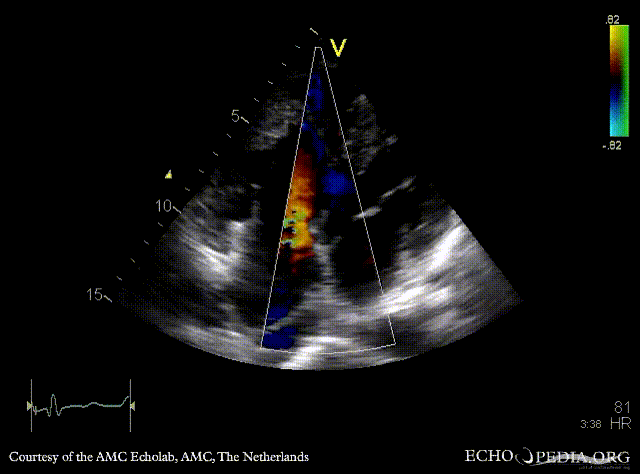

Large VSD, syndrome of Eisenmenger

PLAX: Large VSD

PSAX: Color Doppler of large VSD